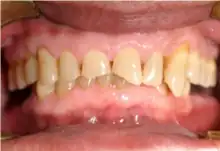

Mouth

Acid reflux into the mouth can cause breakdown of the enamel, especially on the inside surface of the teeth. A dry mouth, acid or burning sensation in the mouth, bad breath and redness of the palate may occur.[27] Less common symptoms of GERD include difficulty in swallowing, water brash, chronic cough, hoarse voice, nausea and vomiting.[26]

Signs of enamel erosion are the appearance of a smooth, silky-glazed, sometimes dull, enamel surface with the absence of perikymata, together with intact enamel along the gum margin.[28] It will be evident in people with restorations as tooth structure typically dissolves much faster than the restorative material, causing it to seem as if it "stands above" the surrounding tooth structure.[29]